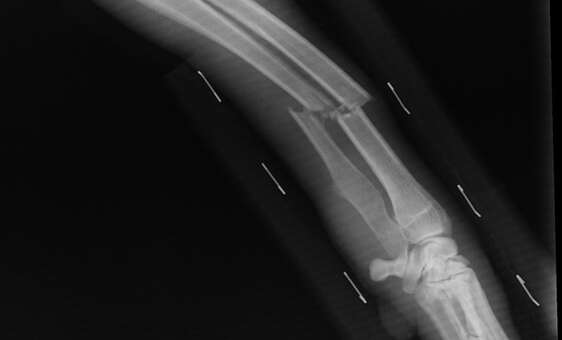

W Polskim prawie karnym w sprawach o przestępstwa uszczerbku na ciele o kwalifikacji prawnej decydują konsekwencje, a nie zamiary sprawcy